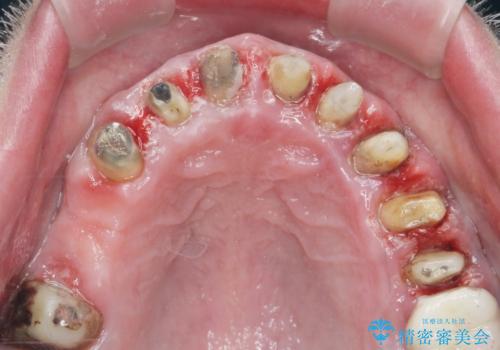

- 「セラミック治療を他院で受けたが、それ以来歯ぐきが腫れ違和感がある、改善してほしい。」と歯ぐきの状態改善を希望され来院されました。

歯周組織検査を行うと歯ぐきからは容易に出血し、X線検査より歯とセラミッククラウンの適合が悪い(ピッタリと合っていない)状態が示唆され、歯ぐきの炎症を惹起している状態でした。

セラミッククラウンを除去し仮歯を装着し、歯周外科手術を行い歯ぐきの状態を改善したのち、適合の良いセラミッククラウンを再作製をする治療計画としました。